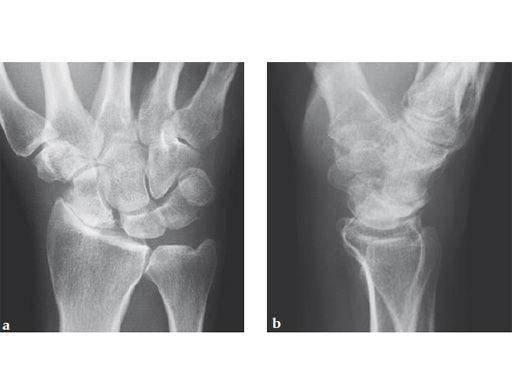

Case 1: SNAC wrist stage 3. Operative procedure and technical details.

Case provided by Ladislav Nagy, Zrich, Switzerland, and Fiesky Nez, Valencia, Venezuela.

Fig 1ab Preoperative x-rays. Notice the midcarpal joint destruction and the DISI deformity of the lunate.